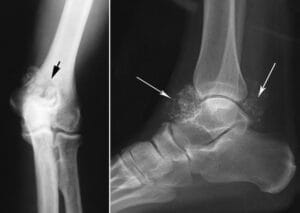

In these X-rays of the elbow joint (left) and ankle joint (right), the loose bodies associated with synovial chondromatosis are clearly visible.

(Left) Reproduced from Johnson TR, Steinbach LS (eds.): Essentials of Musculoskeletal Imaging. Rosemont, IL, American Academy of Orthopaedic Surgeons, 2004, p. 297.